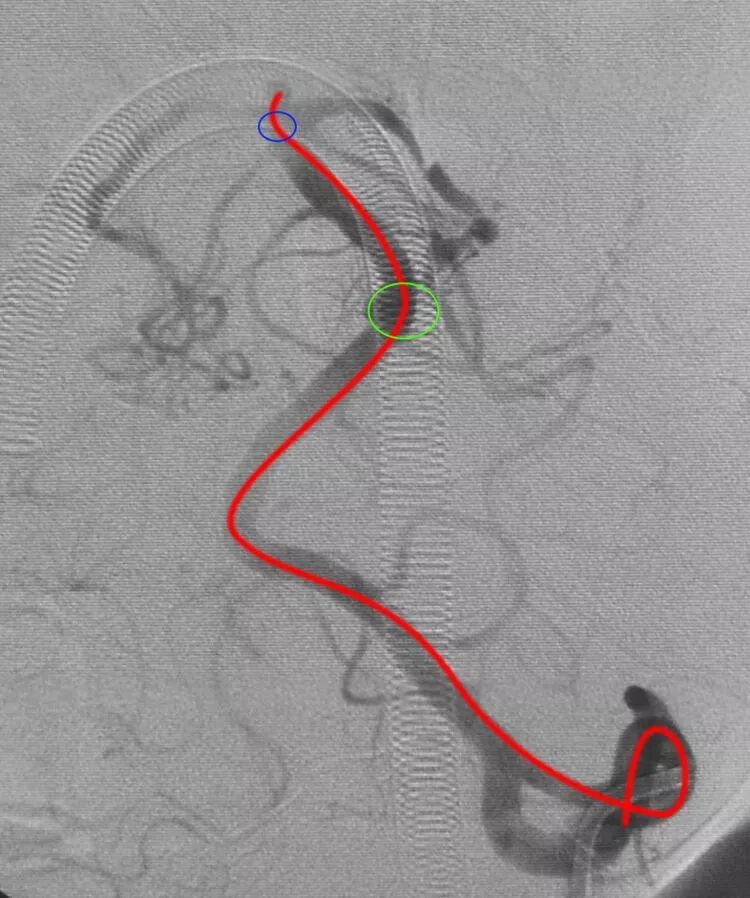

后交通动脉瘤,朝外下方生长,欲把微导管头塑成C形,需塑两个弯儿,第一个弯儿(蓝箭头)顺应动脉瘤体和颈内动脉C1段的成角,第二个弯儿(绿箭头)顺应颈内动脉虹吸弯前膝的弯度,更近心端的弯儿(黑箭头)不用塑形,是微导管在载瘤动脉内的自然成形

栓塞后的工作位造影和蒙片